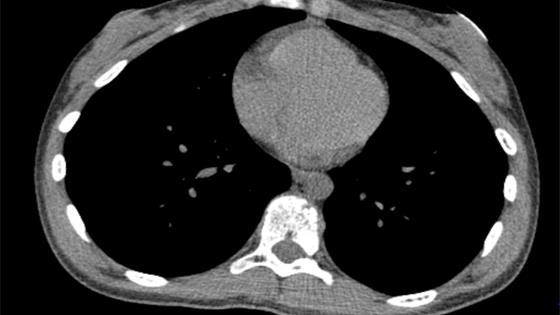

肺功能检查根据常规肺功能检查基层指南,包括有肺通气功能检查 、支气管激发试验、支气管舒张试验、肺弥散

肺灌注显像可由静脉注射放射性核素标记物的颗粒,颗粒进入肺部血管后可出现显影,用于了解肺部各个部位的血

肺动脉造影(CPA)可用于判断虽然是诊断肺栓塞的“金标准”,但属于有创检查需要通过导管穿刺进入静脉插